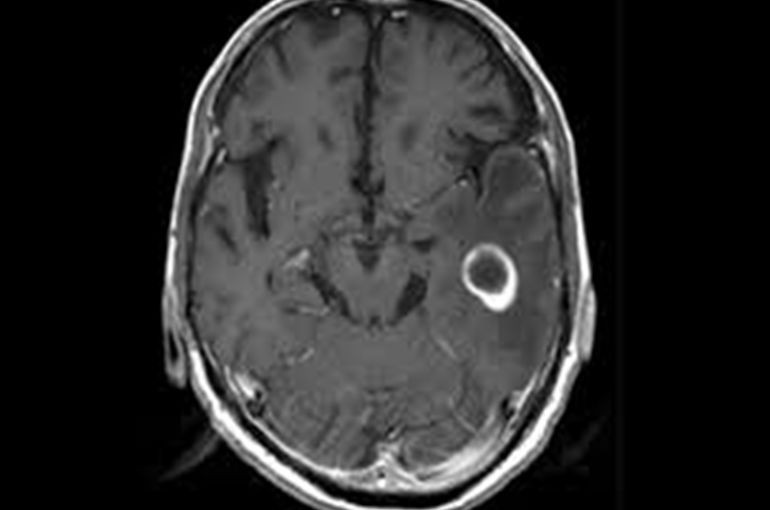

□脳腫瘍

脳腫瘍がある時の特徴して、

・頭痛や頭の重い感じが徐々に悪化し、吐き気がないのに突然吐く

・目がかすむ

・特に朝頭痛が起きやすい

といった特徴があります。

これらの特徴は脳収容の疑いがあります。